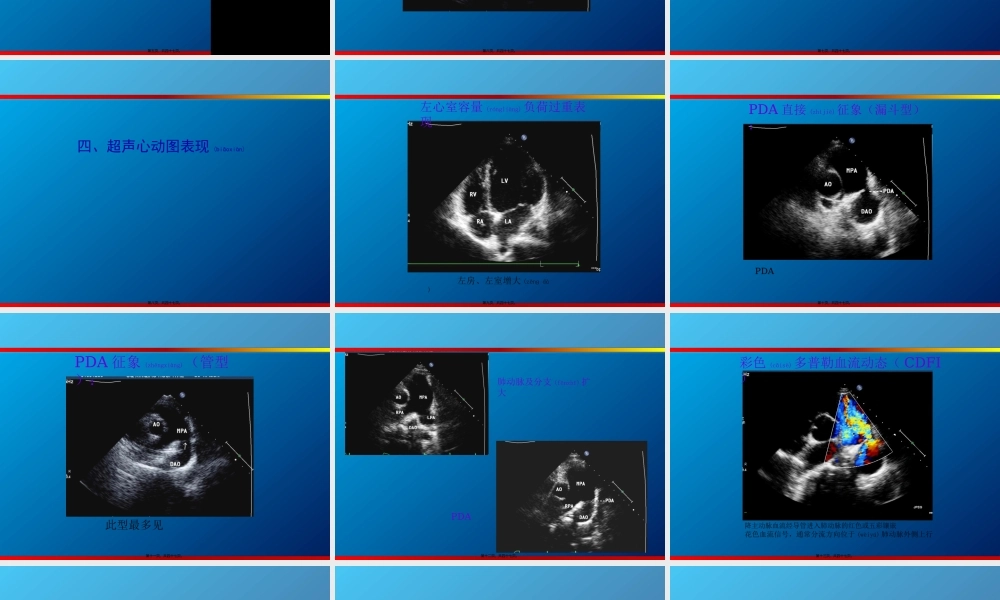

2、本站所有内容均由合作方或网友上传,本站不对文档的完整性、权威性及其观点立场正确性做任何保证或承诺!文档内容仅供研究参考,付费前请自行鉴别。

3、如文档内容存在违规,或者侵犯商业秘密、侵犯著作权等,请点击“违规举报”。

碎片内容

蜗牛文库的最新文档

二年级数学下册其中检测卷二年级数学下册其中检测卷附答案#期中测试卷.pdf

10.00金币

0下载